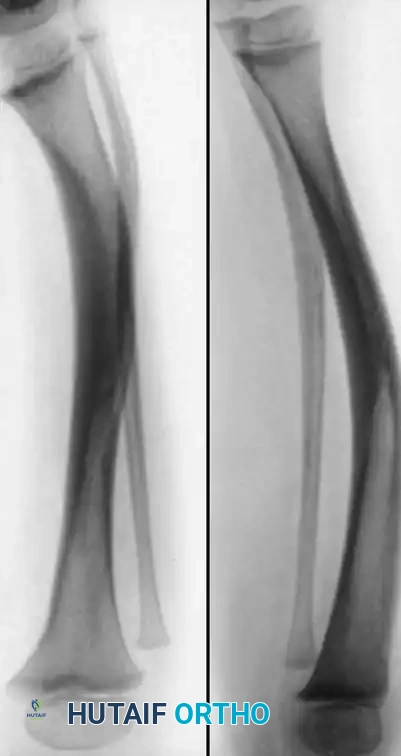

Fig. 26-54 Type II congenital pseudarthrosis of tibia. Note anterior bowing and narrow, sclerotic medullary canal.

Fig. 26-55 Type III congenital pseudarthrosis of tibia. Note cyst formation in middle third of tibia with anterior bowing.

Fig. 26-56 Type IV congenital pseudarthrosis of tibia. Note fracture in anterior cortex in distal third of tibia.

Clinical example demonstrating intramedullary stabilization of a tibial pseudarthrosis. Note the central placement of the rod spanning the dysplastic segment.

Radiographic follow-up showing incorporation of bone graft and maintenance of alignment following intramedullary fixation.